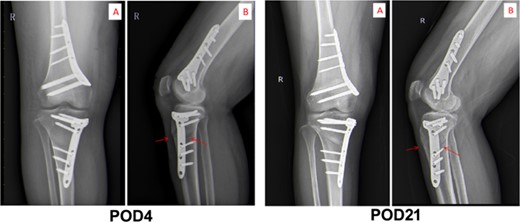

The third day postoperation (POD3), the patient still had a fever with a temperature up to 38.6°C. Blood test results indicated the CRP level and WBC count of this patient rose to 110.42 mg/L and 9.99 × 109/L, respectively (as shown in Fig. 2). Additionally, the patient complained of incision pain and slight swelling of the lower extremities. Four days after surgery (POD4), computerized tomography (CT) scans of the right knee joint indicated degenerative changes of the joint and slight swelling of its surrounding soft tissues after osteotomy (as shown in Fig. 3). Afterwards, physical examination of the patient detected a little effusion after surgical dressing removed, and the surrounding tissue depicted a symptoms of redness, swelling and heat.

Computed axial tomography of chest. The images of CT scan on POD4 and POD21.

After therapy, the patient’s body temperature got back to normal. In addition, the WBC count, neutrophils ratio, CRP level and interleukin-6 content were all returned to normal range. On postoperative day 13, the patient was in good condition and the excipients in the operation area were bandaged and fixed well. Additionally, the surgical incision was well closed, dry and without exudation. Furthermore, there was no redness, swelling, heat, or pain in the incision. The lower limbs were equal in length, without varus or valgus deformity, and the function of the knee flexion or extension was in good order. After discharge, linezolid was continued orally for 4 weeks until physical reexamination. Twenty-one days post-operation (POD21), the patient went back to hospital for physical re-examination. Consequently, she declared no pain in the surgical incision and no swelling of the lower extremities (Fig. 2). The CT results of reexamination indicated the following phenomenon: (i) The changes of right knee joint after osteotomy were degenerative; (ii) nodular high-density image in the lower part of the right femur, which manifests the formation of bone islands (Fig. 3).